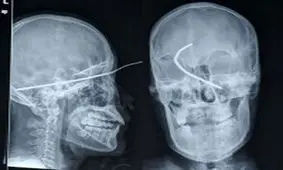

پرتوهای اشعه ایکس دستگاه های رادیولوژی و سی تی اسکن دارای عوارض سرطان زاهستند.